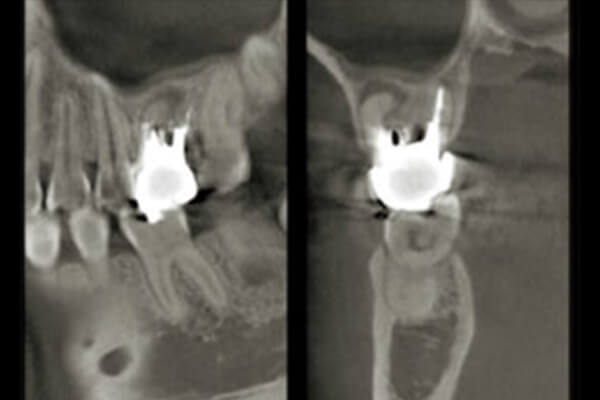

●解析力:3次元での画像解析が可能になる

●可視性:通常のレントゲンでは見れない領域まで見る事が出来る

骨の厚みや量を診断した上で

インプラントの埋入計画が可能

通常のデジタルレントゲンでは

解析が難しい範囲も分析可能